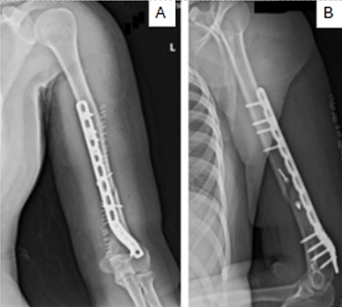

A Rare Clinical Dilemma: Humeral Shaft Fracture in a Full-Term Pregnant Patient – A Case Report with Review of Literature

Laxman Choudhary , Amandeep Bains , Akshant Chandel , Samarjanki Rymbai , Amir Suhail , Debdeep Majumdar

………………………………p.178-184